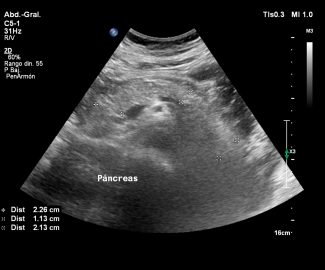

Especialista en diagnóstico por imágenes con más de 25 años de experiencia en el campo del ultrasonido y radiología digital. Trabajamos con equipos de alta tecnología garantizando la calidad y seguridad de nuestros diagnósticos, pues nuestra prioridad es la salud, bienestar y satisfacción de nuestros pacientes.

Sabemos que visitar un centro médico a veces genera nervios. Por eso, hemos creado un ambiente cálido, moderno y 100% seguro para ti. Desde nuestra cómoda sala de espera hasta nuestras áreas de ecografía, mamografía y rayos X, cada rincón está equipado con tecnología de última generación y diseñado para que te sientas en confianza.